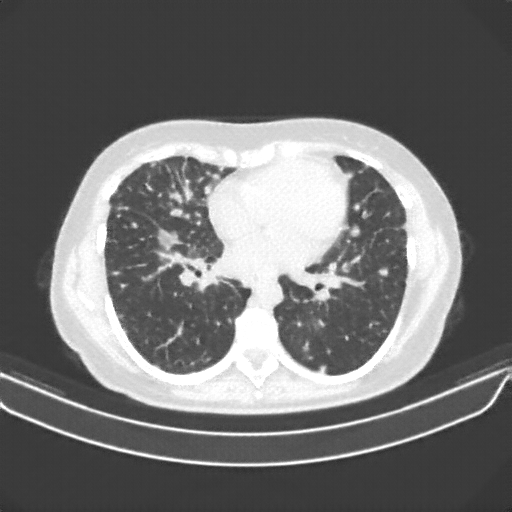

Reconstructed NATIVE CT scan (cycle consistency)

No window - Raw intensity values

Lung window (WL -600, WW 1500 β†’ Low βˆ’1350, High +150)

Targeted Slice 70 - Lung Window Analysis (Generated vs Real Venous)

0.752

Lung SSIM

110.9

Lung RMSE

46.5

Lung MAE

Average Lung Window Metrics Across All Slices (133 slices) - Generated vs Real Venous

0.749

Lung SSIM (Avg)

109.7

Lung RMSE (Avg)

44.6

Lung MAE (Avg)